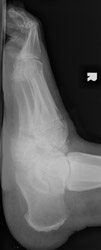

Charcot Joint: AP -Charcot Joint: Lateral - Disorganization of Chopart jointNEUROPATHIC JOINT DISEASE (CHARCOT JOINT) articular degeneration secondary to weight-bearing trauma and neurovascular changes on sensory deficient joint, resulting in bony resorption and formation.

Osteophytes, joint effusions, and soft tissue swelling are among the common early findings. Later in the disease process, acute fractures, dislocations, and subluxations may occur. Subluxations at the tarso metatarsal joints may mimic Lisfranc fracture/subluxations. Frequent fractures include subchondral fractures of the second metatarsal head, and avulsion fractures of the posterior calcaneal tubercle. Tapering osteolysis ("sucked candy" or "pencil-pointing"), bony fragmentation with well defined margins, and fusions with or without pseudoarthroses are other signs of progression.